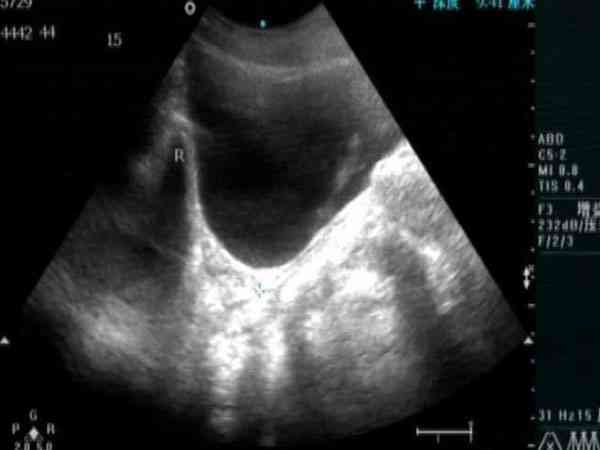

女性始基子宮超聲診斷標準詳解,60%的女性都不知曉

始基子宮又稱痕跡子宮。在胎兒發育時期,女性生殖器官由兩側副中腎管匯合而來,始基子宮系兩側副中腎管匯合後不久即停止發育所致,常合併無陰道。這種子宮極小,僅1~3釐米長,多無宮腔、無子宮內膜,無月經來潮。陰道四維彩超,可以清晰地看到始基子宮的影像,始基子宮很小,似一條索狀,無宮腔波。始基子宮由於沒有宮腔、沒有子宮內膜,不會有月經來潮。始基子宮的診斷可依靠電子陰道鏡,腔內四維彩超,染色體分析和電化學發光...

通過做B超檢查是能確認10歲的兒童是否存在始基子宮的。在超聲檢查下面會發現有始基子宮的影像,顯示子宮一般只有1~3cm,似一條索狀,無宮腔波。始基子宮又稱痕跡子宮,屬發育異常,始基子宮由於沒有宮腔、沒有子宮內膜,自然不會有月經來潮。如果家長還不放心的話,可以帶孩子做電子陰道鏡,腔內四維彩超,染色體分析和電化學發光法內分泌檢測都可確診。同時,10歲兒童始如果確診為始基子宮後面通過治療也是會有希望重新...